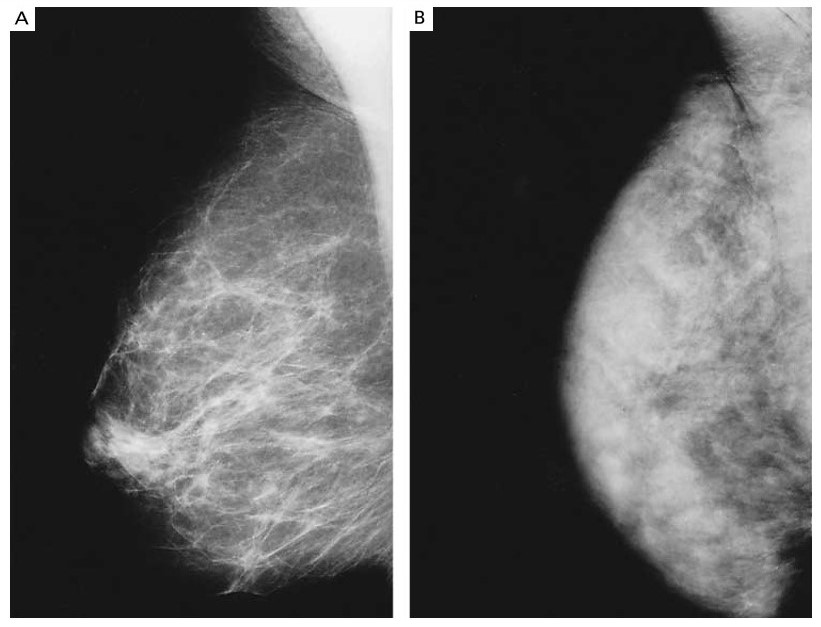

The radiologic appearance of the breast varies depending on the relative amounts of fat, connective tissue, and epithelial tissue. Breast tissue ranges from tissue made up entirely of fat to tissue occupied by diffuse or nodular densities (Fig. 4).[80] These variations in the density of breast tissue on mammography are referred to as the parenchymal pattern of the breast. Parenchymal density has been shown histologically to be inversely correlated with fat content and directly correlated with fibrous- and epithelial-tissue content.[81] Breast density decreases with increasing age, postmenopausal status, increasing number of births, and declining body weight, suggesting that the tissue changes responsible for breast density are under hormonal control.[82,83] Furthermore, women who have dense breasts on mammography have higher serum estrogen concentrations than women with less dense breasts,[84] and estrogen-replacement therapy increases breast density in postmenopausal women.[85]

Figure 4. Mammograms Showing a Normal Breast in One Woman (Panel A) and a Breast with Extensive Areas of Radiographically Dense Tissue in Another Woman (Panel B).

Figure provided courtesy of Dr. K. Bukhanov.

Breast density has been associated with the risk of breast cancer.[19,86,87] With the use of the medical records of 45,000 women assigned to mammography in the Canadian National Breast Cancer Screening Study, a case-control study of 345 women with newly diagnosed cases of breast cancer and 354 controls was performed.[19] The relative risk of breast cancer for the women in the highest category of breast density, as compared with those in the lowest category, was 6.0 (95 percent confidence interval, 2.8 to 12.9).[19] In several studies of women with family histories of breast cancer, increased breast density on mammography was more common than expected,[88,89] suggesting that it may be genetically determined, at least in part,[90] but this association has not been confirmed by other studies.[86,87,91]

Treatment with tamoxifen is associated with a reduction in breast density in both premenopausal and postmenopausal women,[84,92] as are a low-fat, highcarbohydrate diet[82] and the administration of gonadotropin-releasing hormone, which inhibits ovarian secretion of estrogen.[84] However, the reduction in breast density in association with these factors has not yet been correlated with a reduction in the risk of breast cancer. If such a correlation is demonstrated, breast density on mammography could become useful for evaluating antiestrogenic and other chemopreventive therapies.